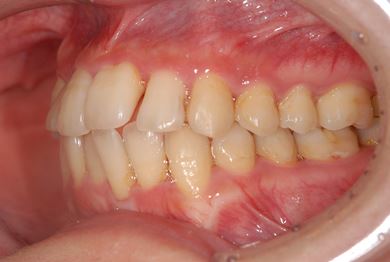

治療前

• 治療前